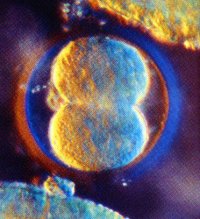

Fertilization has occurred! The sperm and the egg have discovered each other in the Fallopian tube. A unique human being has been created with 46 chromosomes which will determine the person's physical characteristics.